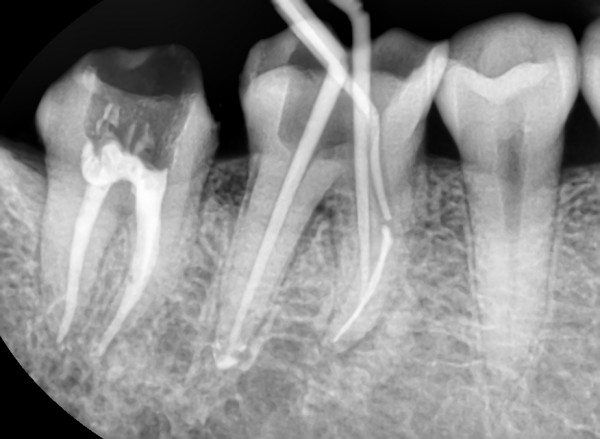

치과치료 중 신경치료는 극도로 상한 치아를 발치하기 전 시행하는 최후의 치료 방법입니다. 따라서 경우에 따라 완치가 불가능할 경우 치아를 발치할 수도 있습니다.

1. 치료 : 신경치료는 머리카락과 같은 미세한 치아신경을 수차례 제거하고 소독한 후, 인공신경으로 교체하는 매우 까다로운 치료입니다.

신경치료는 일반적으로 3~4회 정도 치료를 받지만, 치아부위와 상태에 따라서 치료횟수가 늘어날 수 있습니다.